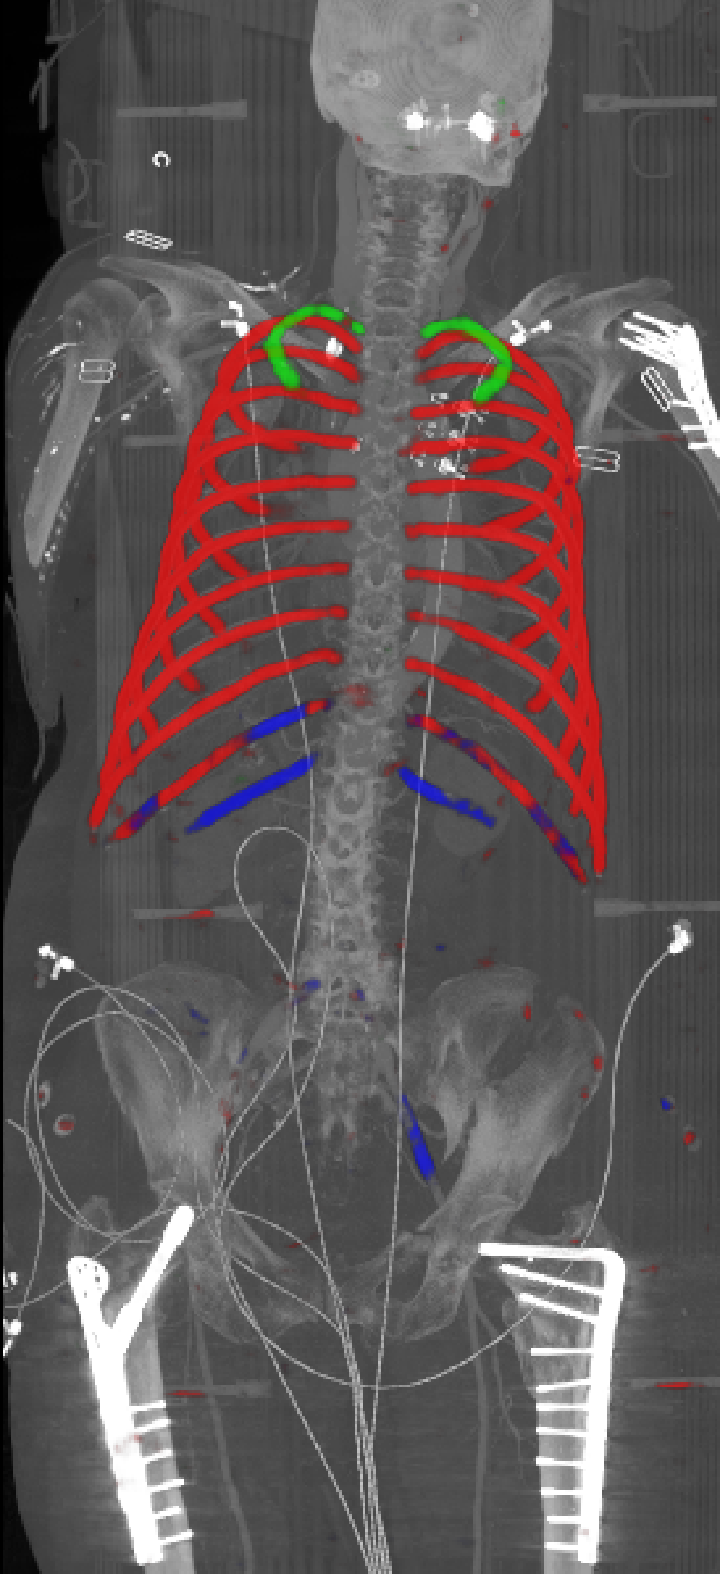

As can be seen from Table 2, we obtain overall good performance for the overall rib detection captured for example with an mean Dice of 0.84. Let us remark that for thin objects, such as the dilated rib centerlines, the Dice score constitutes a rather sensitive measure. The results indicate that detecting the first and twelfth rib pairs is more difficult for our network. While extraction of the first rib is more challenging due to, e.g., higher noise in the upper thorax or other bony structures in close vicinity (clavicle, shoulder blades, vertebrae), the twelfth rib can be extremely short and is easily confused by the neighboring ribs. For further illustration, Figure 4 shows the results on selected representative cases. Generally, the ribs are well detected without major false responses in other structures - despite all the different challenges present in the data. The color coding highlighting of the multi-label detection reveals that first and twelfth are mostly correctly detected. In few cases the network wrongly generated strong responses of the classes first rib or last rib for voxels belonging to the second or eleventh rib pair.

Refer to caption

Figure 5: Automatically generated centerline splines associated with the FCNN outputs displayed in Figure 4. The selected case above display common difficulties which are inherent in the data set, such as pads (a) or cables (b), internal devices such as pacemakers (c), stents (d), spinal (e) and femural/humeral implants (f), injected contrast agents (g), patient shape variations such as scoliosis (h), limited field of views (FOVs), i.e. partly missing first (i) or twelfth rib (j).